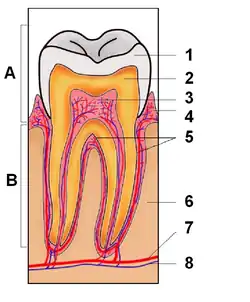

Zahnpulpa

1 = Schmelz

2 = Dentin

3 = Pulpencavum mit Pulpa

4 = Gingiva

5 = Wurzelzement

6 = Alveolarknochen

7 = Arteria alveolaris

8 = Vena alveolaris

Nervus Alveolaris (nicht eingezeichnet)

A = Zahnkrone; B = Zahnwurzel